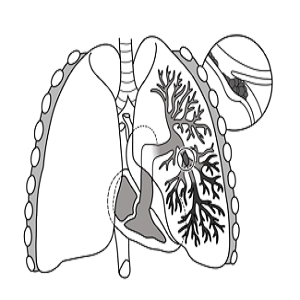

Pulmonary embolism (PE) is a blockage of an artery in the lungs by a substance that has moved from elsewhere in the body through the bloodstream (embolism). Symptoms of a PE may include shortness of breath, chest pain particularly upon breathing in, and coughing up blood.Symptoms of a blood clot in the leg may also be present, such as a red, warm, swollen, and painful leg.<br />PE usually results from a blood clot in the leg that travels to the lung. The risk of blood clots is increased by advanced age, cancer, prolonged bed rest and immobilization, smoking, stroke, long-haul travel over 4 hours, certain genetic conditions, estrogen-based medication, pregnancy, obesity, trauma or bone fracture, and after some types of surgery. A small proportion of cases are due to the embolization of air, fat, or amniotic fluid.<br />Diagnosis is based on signs and symptoms in combination with test results. If the risk is low, a blood test known as a D-dimer may rule out the condition.Otherwise, a CT pulmonary angiography, lung ventilation/perfusion scan, or ultrasound of the legs may confirm the diagnosis. Together, deep vein thrombosis and PE are known as venous thromboembolism (VTE).<br />Management <br />Efforts to prevent PE include beginning to move as soon as possible after surgery, lower leg exercises during periods of sitting, and the use of blood thinners after some types of surgery. Treatment is with anticoagulants such as heparin, warfarin or one of the direct-acting oral anticoagulants (DOACs). These are recommended for at least three months. Severe cases may require thrombolysis using medication such as tissue plasminogen activator (tPA) given intravenously or through a catheter, and some may require surgery (a pulmonary thrombectomy). If blood thinners are not appropriate, a temporary vena cava filter may be used.<br /><br />